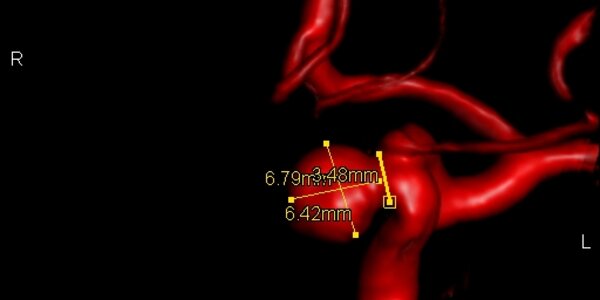

Life Threatening Aneurism - Surgery Monday, Home Tuesday With A Band Aid

Norma Wooley checked into Loyola University Hospital on a recent Monday morning for brain surgery to repair a life-threatening aneurism (also: aneurysm).  She went home on Tuesday, cured of the slurred speech, drooping face and worst headache of her life. Wooley had a cerebral aneurism, a weak spot in a blood vessel that balloons out and fills with blood. About six million Americans -- 1 in 50 people -- have brain aneurisms that could rupture. Each year, aneurisms burst in about 25,000 people, and most die or suffer permanent disabilities, according to the Brain Aneurysm Foundation. Dr.…